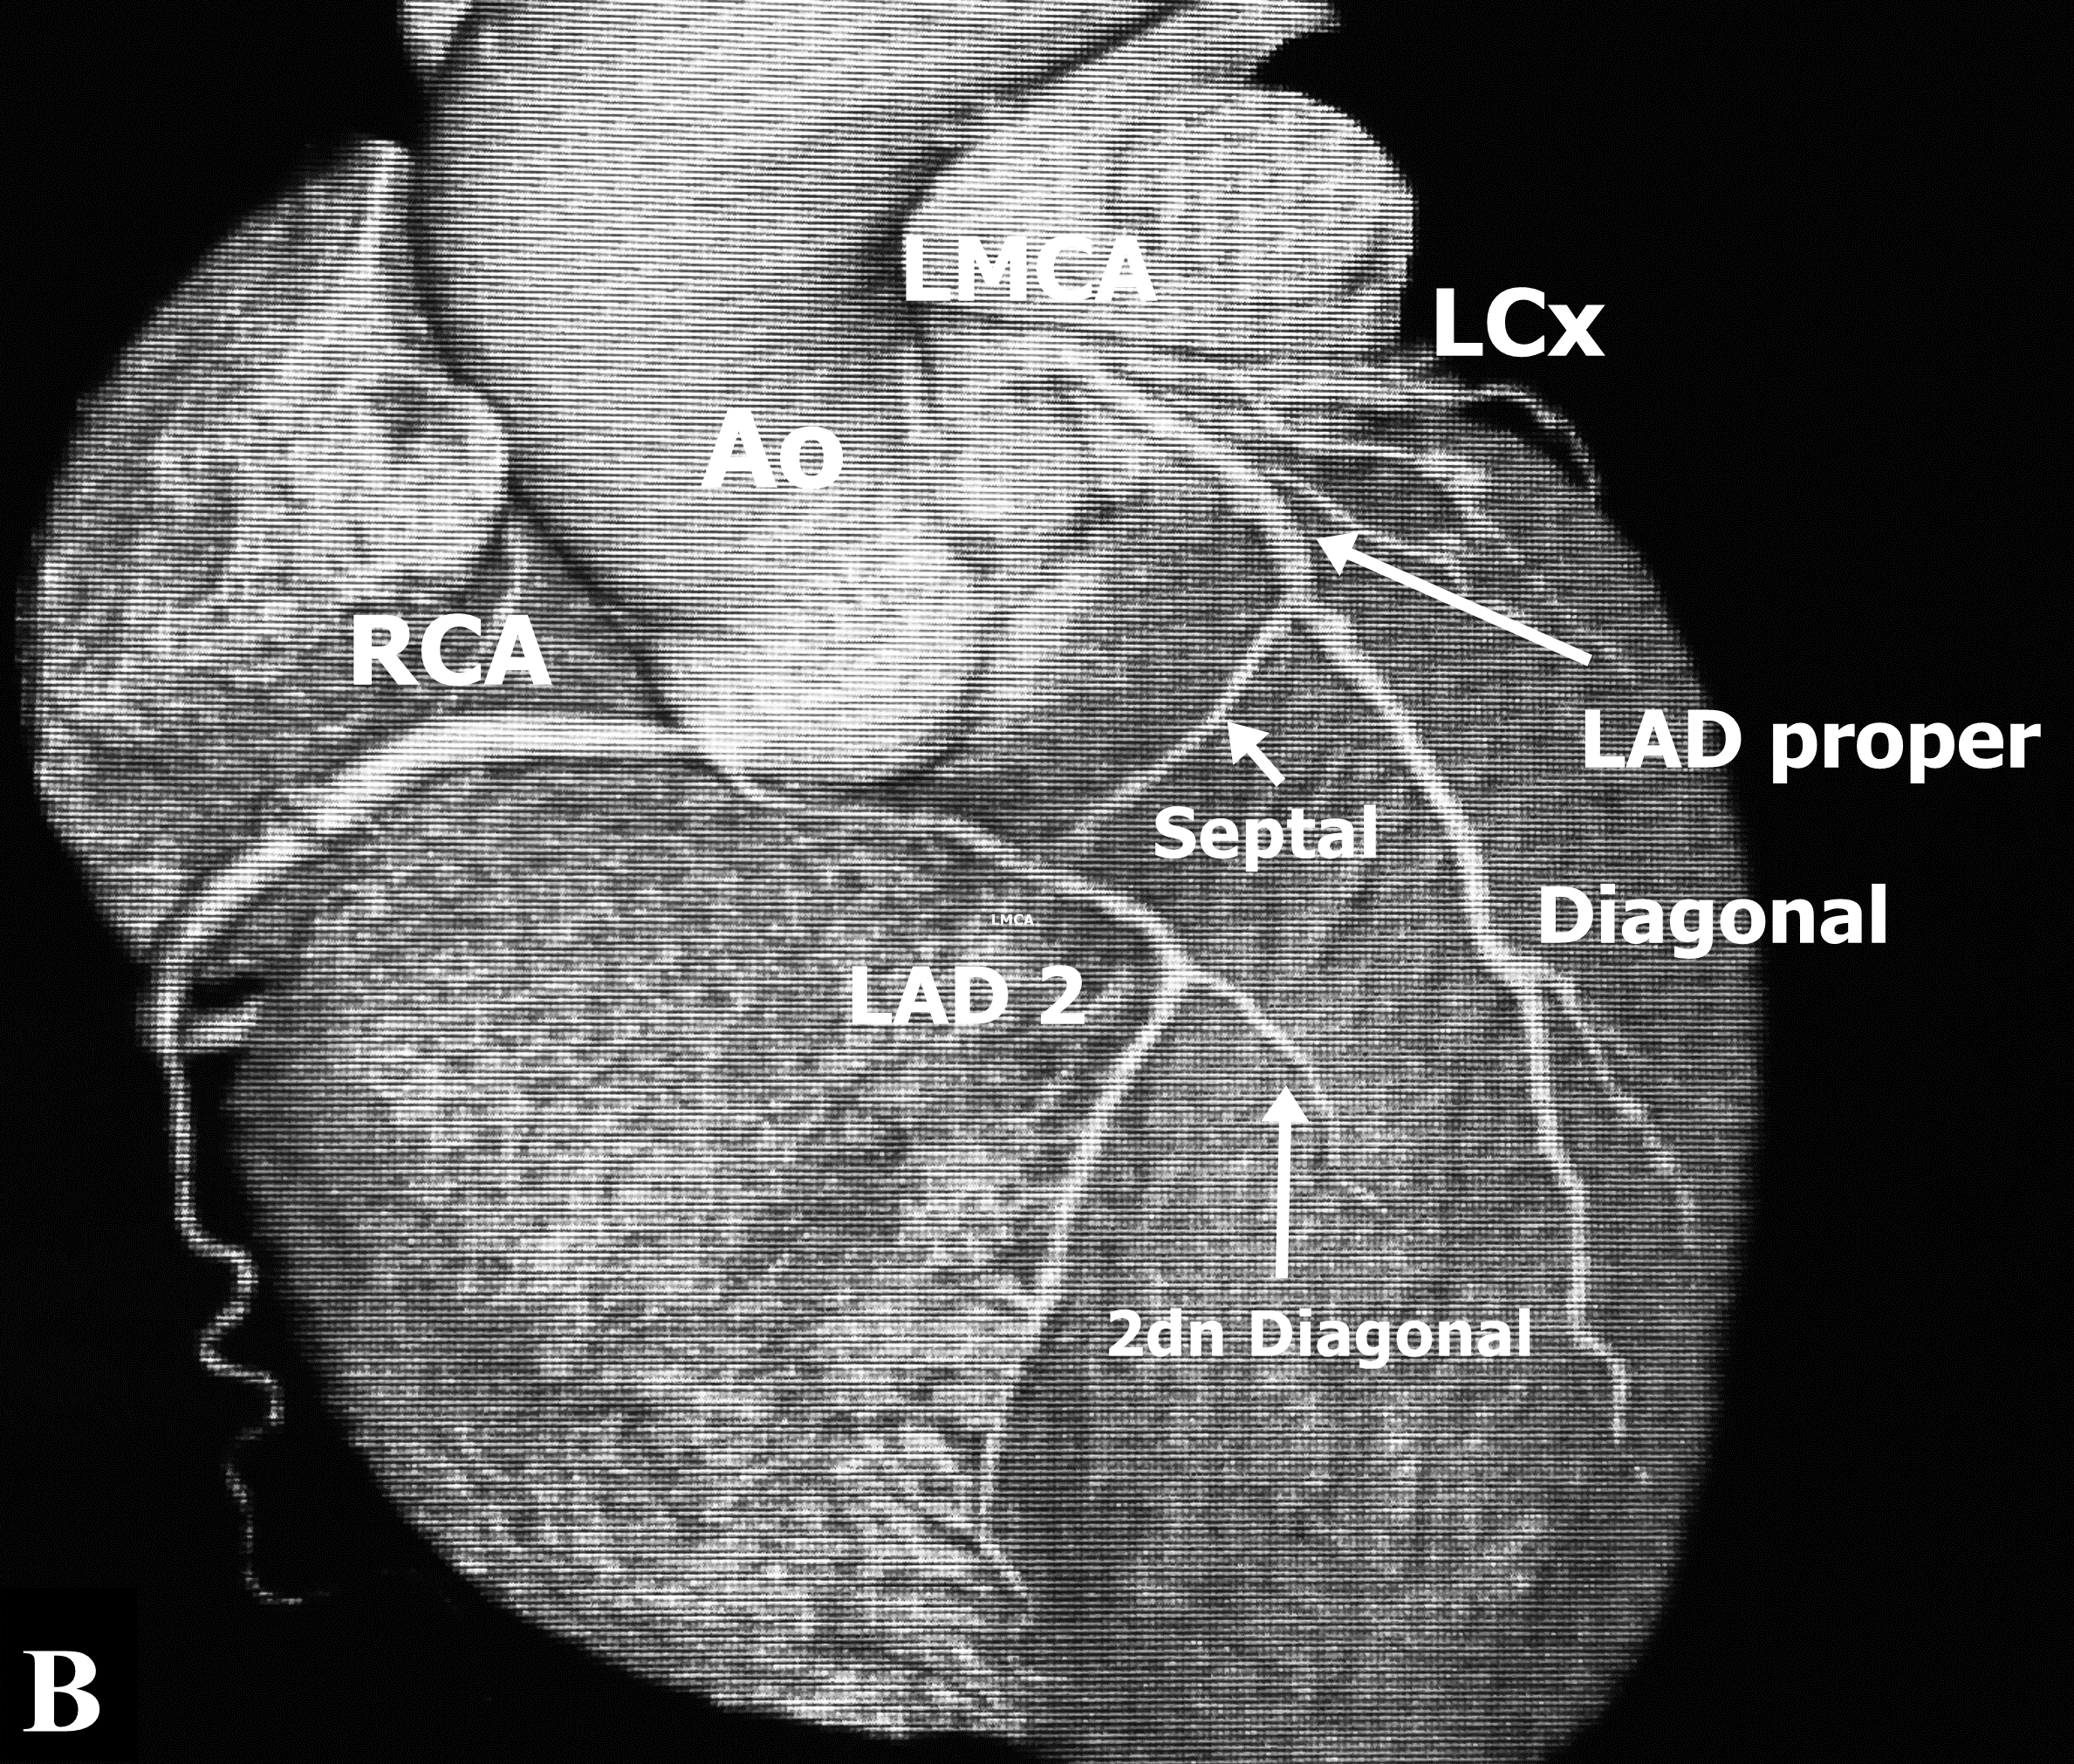

Selective right coronary angiography revealed a dominant right coronary artery (RCA), without lesions (Figure 1B), during the injection, contrast media dyes unselectively an artery that comes very close to the origin of the RCA. Selective angiography of this vessel reveals that it is the middle - distal segment of the LAD which is directed right to left and return to its position on the AIVS giving a septal branch near its origin and a second diagonal branch (Figure 1D) establishing the diagnosis of a dual LAD system (Figure 1C), the proximal segment of the long LAD was narrower than the middle segment without an arteriosclerotic lesion and no compression was observed during systole. CT angiography identified the anomalous origin of long LAD from the Right Valsalva Sinus (RVS) near the origin of the RCA, and passing between the aortic root and RVOT providing a second diagonal branch without atherosclerotic lesions (Figure 2A&2B), and ending in the distal AIVS. The lesion in the posterolateral branch was successfully treated with the implant of 3.0 x 28 mm everolimus eluting stent.

Figure 1: A. Angiographic view of Left Coronary Artery in RAO. LMCA: Left main coronary artery. LAD: Left anterior descending artery. LCx: Left circumflex artery. B. Right coronary artery in LCO. C. Angiographic view in LCO of Left coronary artery. LMCA: Left main coronary artery, LAD 1: Short Left descending artery, LCx: Left coronary artery. D. LAD 2: Long Left anterior descending artery, RCA: Right coronary artery.